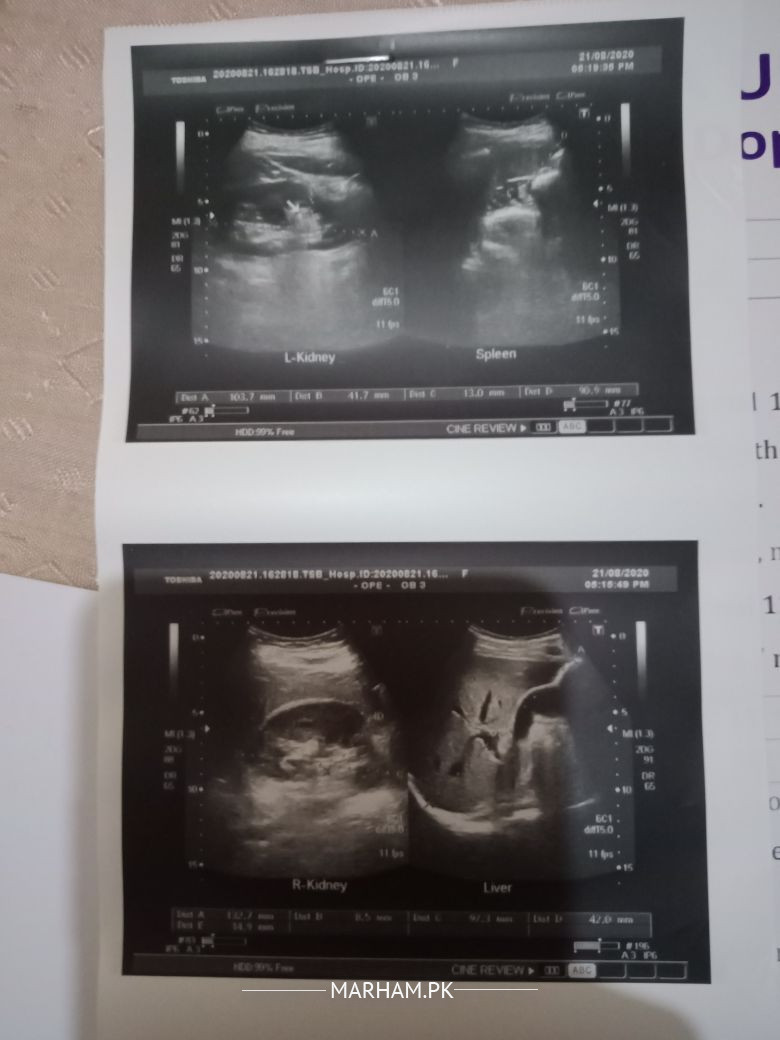

Phir mene Top Multan Nephrologist ko check up karwa .... unho nai Ultrasound karwaya.... Aur medicine di....

You might have another stone,that can be missed b ultrasound, so u may need ct kub after consultation

Well you have just some concterions and rest of your all labs are normal. So better do an CT KUB . It may looks more musculoskeletal pain rather to renal conception. However please use